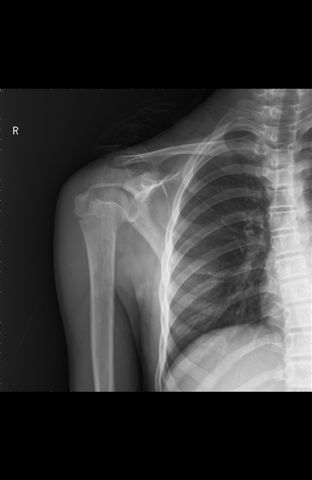

1月前复查:

第一片及一月前复查片肱骨外科颈下内缘均象有骨折,因为每次肱骨体位不同所显示不同,应维持考虑骨折诊断,建议复查或作ct或mri检查。

这么年轻,果是骨折48天也应该有骨痂生成吧,而不是像现在:样低密度影这样光滑

我院ct诊断结果考虑骨骺线。